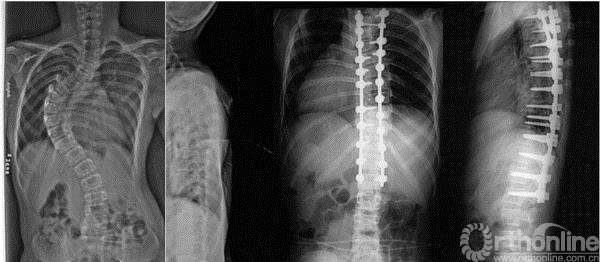

13岁女性患儿,特发性脊柱侧凸(双胸弯,Lenke分型2A-)。术前侧凸角度达80°,行单一后路手术,选择性融合,最大限度保留腰椎活动度